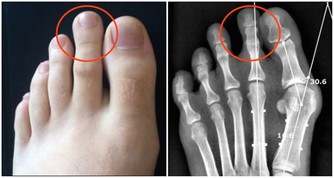

人為什麼會做春夢、被鬼壓床? 這8 種夢或是疾病信號

當然,必須強調的是,這張圖目前主要是根據醫生經驗判斷得出的,疾病導致了某某夢境,僅僅是有可能性,並不一定準確。

覺得自己身體不舒服,最好的辦法還是親自去醫院看醫生,做檢查,得到確切的診療。